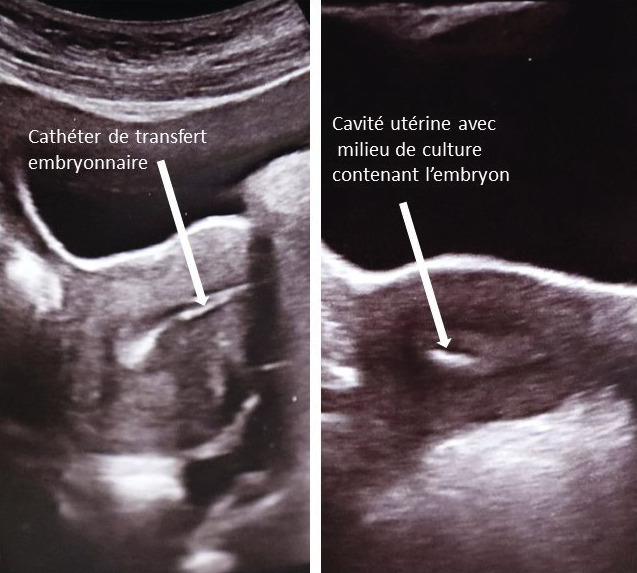

Transfert embryonnaire

Un ou deux embryons sont transférés dans la cavité utérine à l’aide d’un cathéter de transfert adapté (fig. 6 et 7). Afin d’éviter au maximum le risque de grossesse multiple, la plupart des équipes privilégient le transfert d’un seul embryon (single-embryo transfer). Le nombre d’embryons tient compte du choix du couple mais aussi du stade de développement et de la qualité embryonnaire, de l’indication, de l’âge de la patiente et du rang de la tentative. Le transfert embryonnaire est réalisé en ambulatoire ; la préparation de l’endomètre est assurée par la prescription de progestérone (préférentiellement administrée par voie endovaginale, à partir du jour de la ponction).